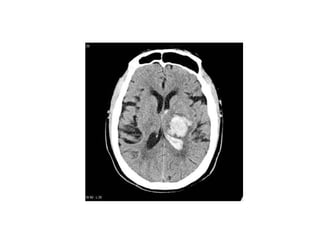

• ECG, CXR (chest pain or dysnea)

• MRI,CT scan of the head(change in mental

status or acute neurological signs indicative of

enceplalopathy/ischemia/intra cranial

hemorrhage)

investigations • ECG, CXR(chest pain or dysnea) • MRI,CT scan of the head(change in mental status or acute neurological signs indicative of enceplalopathy/ischemia/intra cranial hemorrhage) • TTE,TOE,CT with contrast of the aorta (dissection)